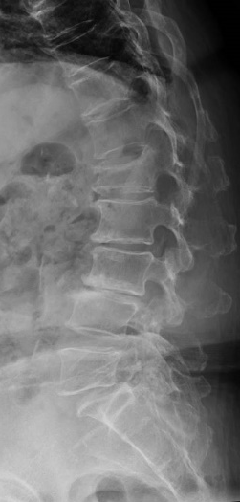

階段状に腰椎が変性すべりをおこしている症例

【術前】

第2, 第3, 第4腰椎に前方への変性すべりを認めます。痛みのため背中を反って立てないことが分かります。MRIではいずれの椎間でも強い脊柱管狭窄が発生し、神経が圧迫されているのが分かります。

【術後】

スクリューとロッド、人工骨を使用した手術により腰椎の階段状変性すべりが整復され、痛みが改善したため腰を反って立つことが出来ています。第2腰椎の前方すべりは軽微であったため、金属は使わず除圧術のみに留めています。